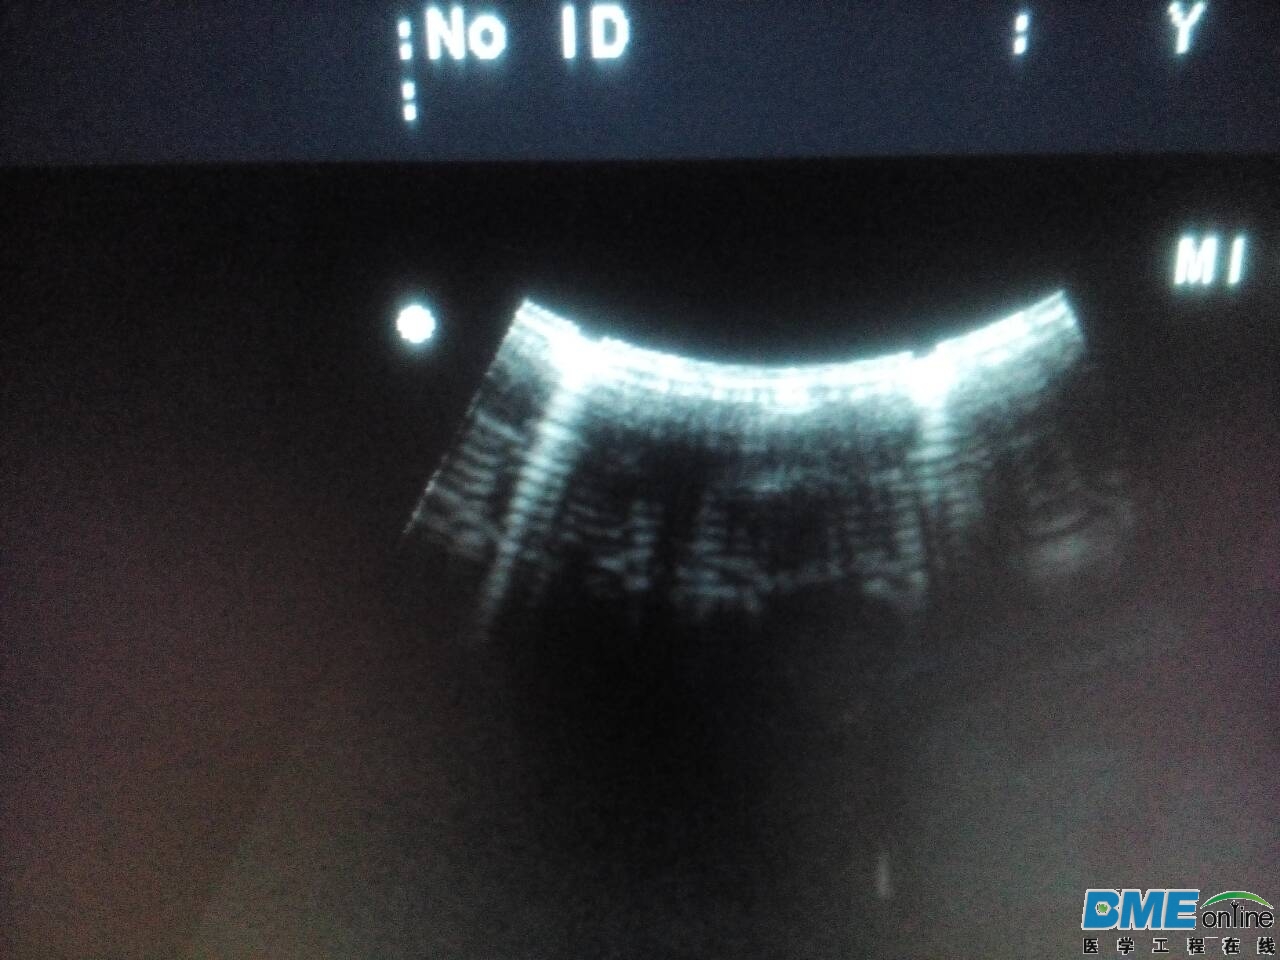

检查图像出现两个对称的的小缺口,切换每个探头都存在。

这应该是阿洛卡的通病,我们这边有台A7,也是类似问题,要换板,

应该是通道板的问题

4950通道板故障,@10的通病。